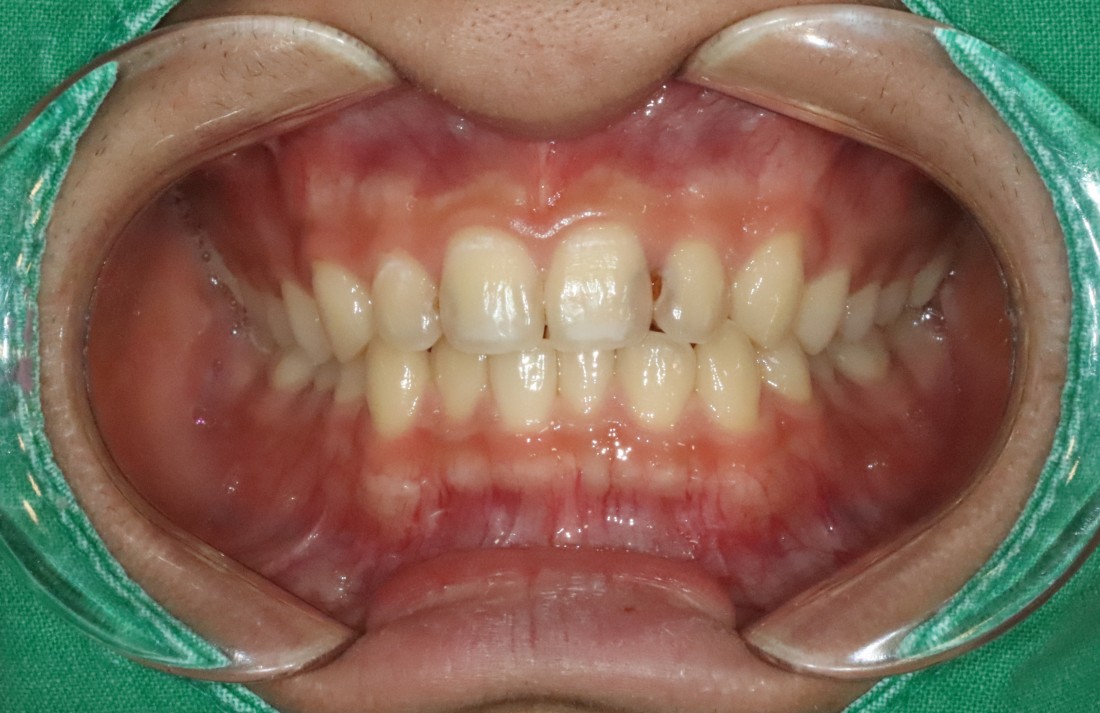

광주 라미네이트를 추천하는 분들은

앞니 컴플렉스가 심하신 분들인데요.

충치로 인해 치아색이 변색되거나

앞니 모양을 고르게 하고 싶으신 분들,

앞니가 벌어진 경우,

치아 크기가 다른 왜소치,

누렇게 변색된 치아 등

다양한 앞니 컴플렉스의 경우에

광주 라미네이트 진료로

환한 미소를 완성할 수 있습니다.